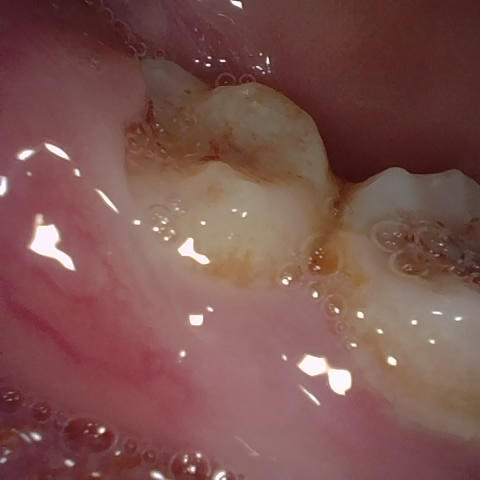

Annotated as "Good"